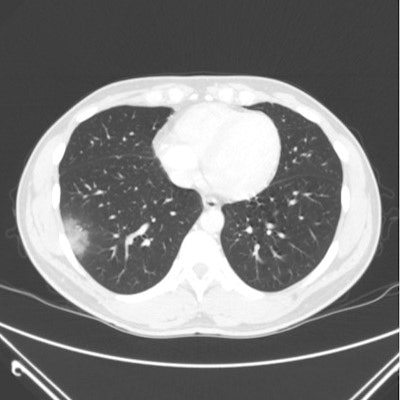

- Radiologists distinguish COVID-19 pneumonia on CT

This article was published during the early days of the COVID-19 pandemic, and it highlights how medical imaging was able to help diagnose patients when early tests with reverse transcription polymerase chain reaction (RT-PCR) were unreliable and slow to produce results. In a paper that ran March 10 in Radiology, radiologists showed that they were able to differentiate COVID-19 from other types of viruses based on the presentation of the disease on lung CT scans.